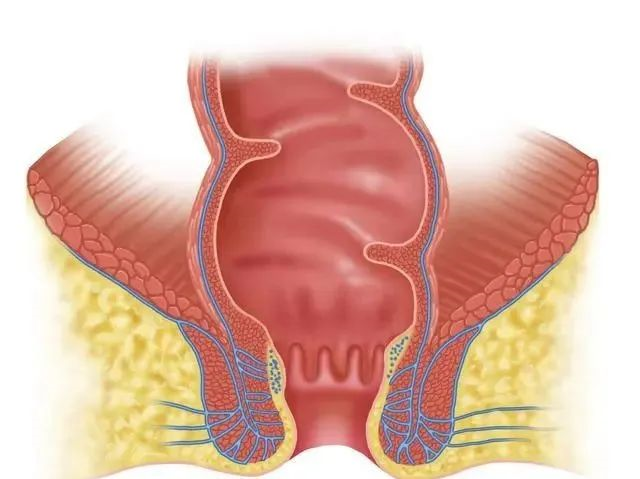

肛瘘是肛肠外科三大疾病之一,肛瘘是由于肛周脓肿破溃以后而形成的一个疾病。

肛瘘有三个部分组成,分别是内口,瘘管和外口。瘘管是比较坚硬的结缔组织,药物治疗是无效的,而内口处于直肠,经常受细菌的感染,愈合是很困难的,因此说肛瘘的治疗是手术治疗,药物治疗是无效的。